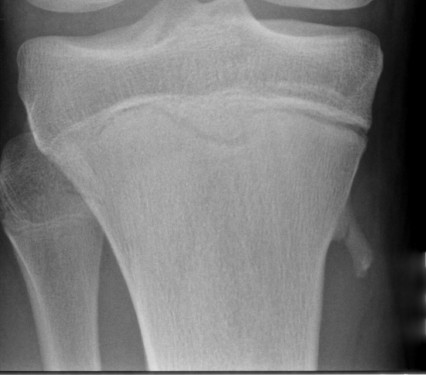

Most common location

- around knee (distal femur / proximal tibia / proximal fibula)

X-ray

Cortical and marrow continuity

Types

1. Pedunculated - has a stalk, points away from joint

2. Sessile - attaches to bone with a broad base

Pedunculated

Protuberant bony lesion arising adjacent to physis

- directed away from joint

- cortical bone and marrow space continuous

Sessile